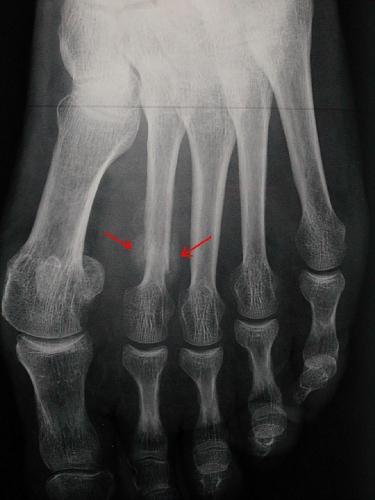

Fracture de fatigue du pied

Pour vérifier la présence d'une fracture de stress, la radiographie n'est pas toujours efficace au début de la fracture, voire jamais dans certains cas. On peut donc utiliser la scintigraphie osseuse, la tomodensitométrie ou l'IRM pour un diagnostic précoce ; ou la radio standard différée d'une dizaine de jours.